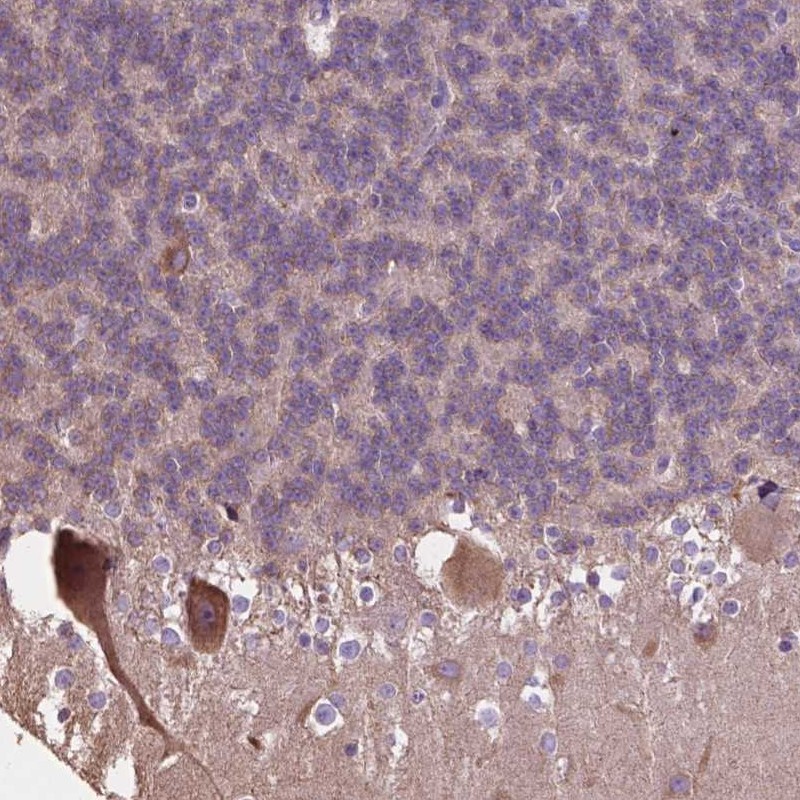

Immunohistochemical staining of human cerebellum shows cytoplasmic positivity in purkinje cells.